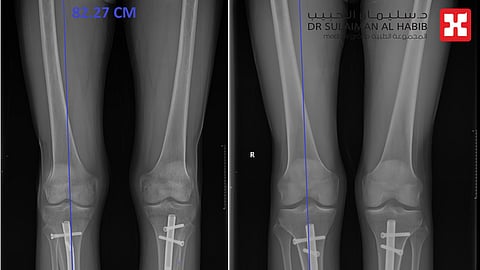

مستشفى الدكتور سليمان الحبيب بالخبر.. نجاح لافت لعمليات تطويل العظام عبر تقنية "المسمار النخاعي"

يواصل مستشفى الدكتور سليمان الحبيب بالخبر، تميزه اللافت في إجراء عمليات تطويل العظام، عبر تقنية المسمار النخاعي الممغنط، والتي تعتبر من أكثر تقنيات تطويل العظام فعالية، وتتسم بأنها تتم دون آلام أومثبتات خارجية تقيد حركة المراجع، وأنهت هذه العمليات معاناة العديد من الحالات من تباين في طول الأطراف السفلية، أوتشوهات القدمين، وكما أنها حققت آمال الأشخاص الراغبين في زيادة طولهم لأهداف متصلة بالتجميل وتحسين المظهر.

ولفت إلى أن العملية تبدأ بزراعة "المسمار المغناطيسي" عبر الأشعة التداخلية، ومن خلال جروح صغيرة لا تتجاوز طولها (1) سم، بعدها يقوم المراجع نفسه وهو في منزله بتشغيل الجهاز بوحدة التحكم الخارجية لمدة لاتزيد عن دقيقتين، فيقوم بإصدار ذبذبات مغناطيسية تسهم في تطويل العظام. مضيفاً أن عملية التطويل تبدأ بعد إجراء الجراحة بخمسة أيام، حيث يتم تطويل العظام بمعدل ملم واحد في اليوم، ومن أبرز مزايا هذه التقنية أنها تحقق نسب نجاح عالية، بالإضافة إلى قصر فترة العلاج بالمقارنة مع عمليات التطويل التقليدية، وعدم وجود آثار خارجيه للعملية، ويتم ازالة المسمار لاحقا بعد مضي سنة ونصف الى سنتين.